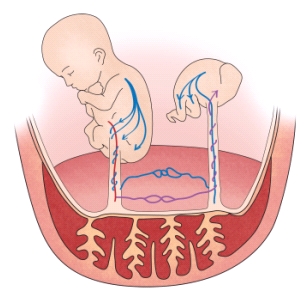

특히 일란성 쌍태 임신에서는 두 태아 사이의 혈관 문합을 통한 혈류의 불균형으로 인한 합병증이 발생할 위험이 있습니다. 태아의 기형이 발생하는 빈도도 더 높습니다. 따라서 16주 이후부터는 2주 간격으로 초음파 검사를 시행해야 합니다.

다태아를 임신한 여성은 뱃속 아기의 수에 비례해 합병증이 생길 확률이 높아집니다. 태반이나 양막의 모양에 따라서 다태아의 합병증이 달라질 수 있습니다. 여러 합병증이 동시에 발생할 수도 있습니다. 혈압 상승, 부종, 단백뇨 등의 증세가 동반되는 자간전증이 발생하기도 합니다. 이는 생명을 위협하는 매우 위험한 합병증입니다. 쌍둥이를 임신한 여성은 단태아를 임신한 여성보다 자간전증을 일으킬 확률이 2배 더 높습니다. 이외에 갑작스러운 체중 증가, 두통, 현기증, 임신 제2기와 제3기 때의 메스꺼움, 구토, 통증, 손발과 얼굴의 부기와 같은 합병증도 있습니다.